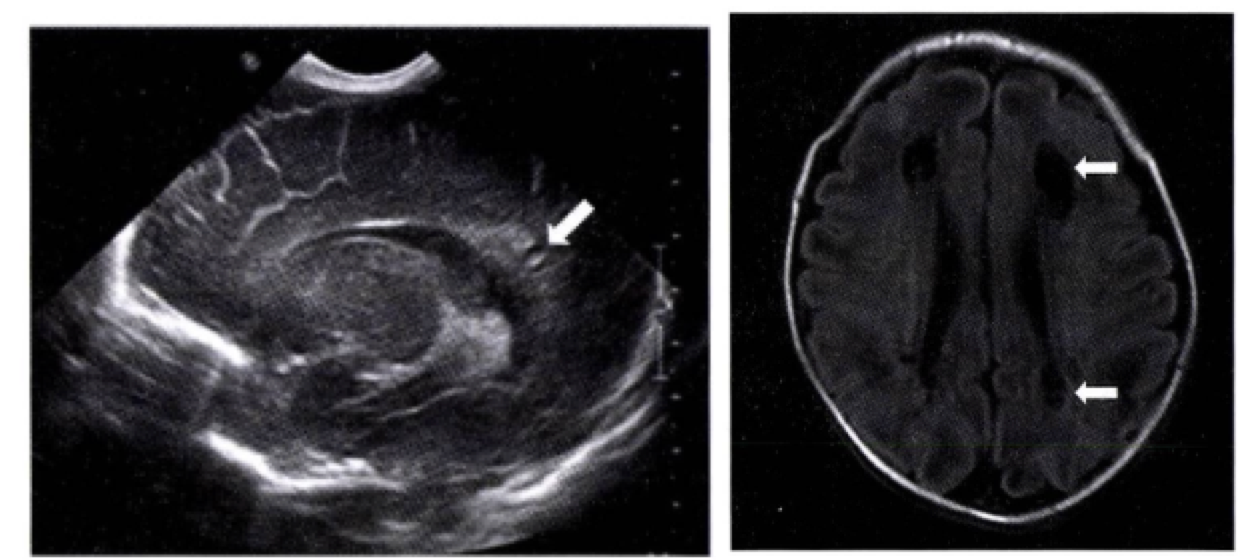

• 정의: 뇌실 주변의 백색질(white matter)에 허혈성 손상이 발생하여 조직이 괴사하고, 이후 낭종(cyst)을 형성하거나 미만성으로 손상되는 질환

• 진단은 뇌 초음파나 MRI 사용

• 뇌 초음파에서는 생후 3-10일 경 뇌실 주변에 고에코 병변이 보이고, 생후 2-3주 후 낭성 변화가 관찰 - 모든 고위험아는 GA 36-40주에 추적 뇌초음파를 실시해야함